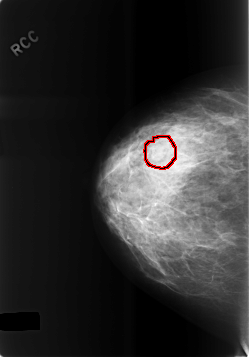

C_0478_1.RIGHT_CC

FILE: C_0478_1.RIGHT_CC.OVERLAY

TOTAL_ABNORMALITIES 1

ABNORMALITY 1

LESION_TYPE MASS SHAPE LOBULATED MARGINS CIRCUMSCRIBED

ASSESSMENT 4

SUBTLETY 2

PATHOLOGY BENIGN

TOTAL_OUTLINES 1

BOUNDARY